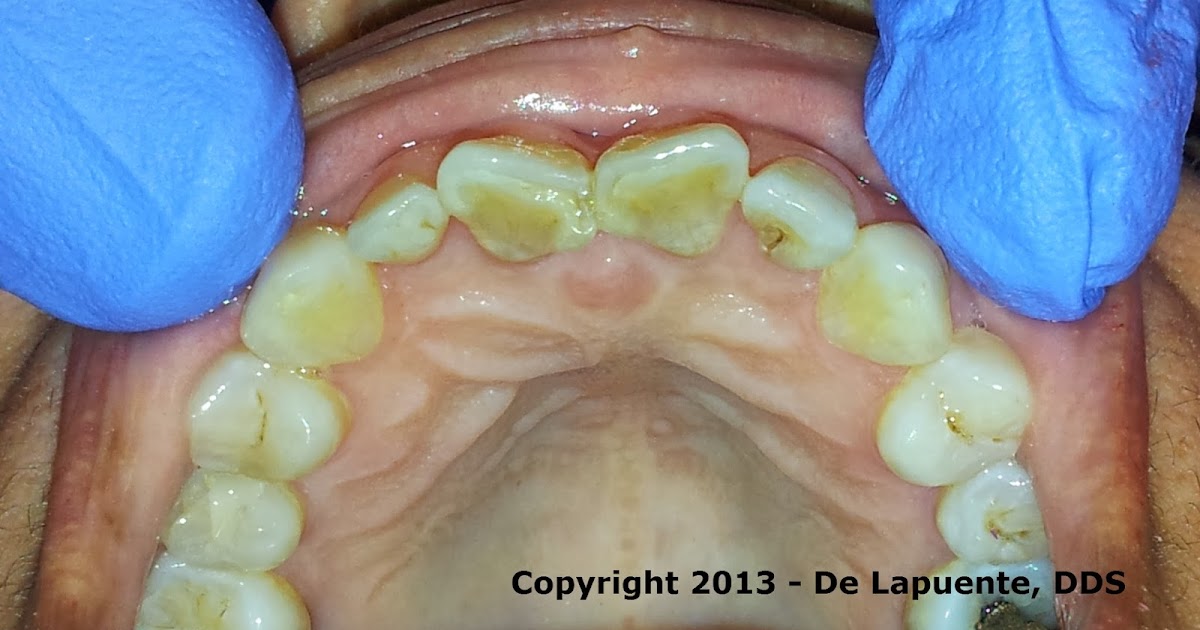

3. Occlusal view of morphological variation in shovelshaped incisors Shovel-Shaped Upper Incisors shovel shape of upper incisors is a common characteristic in asian and. sinodonty is a combination of dental characteristics that includes upper first and second incisors that are shovel. American journal of human genetics 85 ,. shovel shape of upper incisors is a common characteristic in asian and native american populations but is rare or absent in. Shovel-Shaped Upper Incisors.